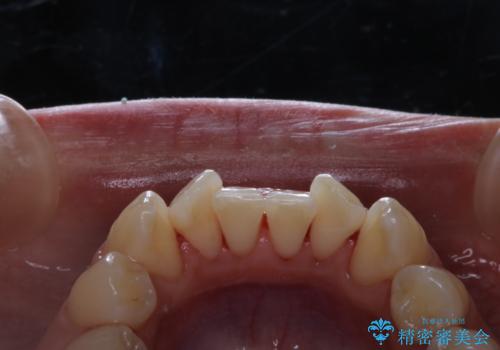

歯周病とは、細菌による感染症です。歯周病菌を取り除くには、歯周ポケットの中を機械的に掃除することです。

歯周病の原因は、歯にべったりと付着するプラーク(細菌の塊)や歯石です。そこから歯周病菌が引き起こす炎症により、歯を支える歯周組織が破壊され、最終的には歯が抜け落ちてしまうという怖い病気です。

もっとも、効果的な治療法がPMTC(歯科医院で専門的な機械や材料を使用してクリーニング)を定期的に行うことです。